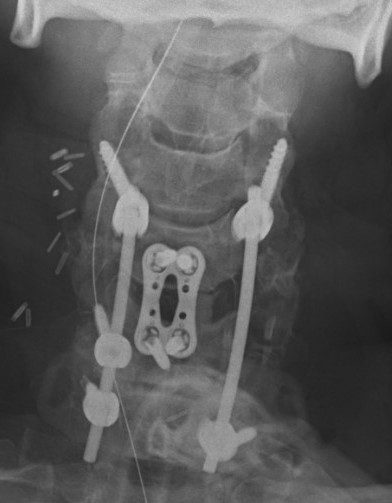

Anterior approach and ACDF

Advantage

- lower infection rates

- simpler patient positioning in multi-trauma patient

- can perform discectomy prior to reduction

Disadvantage

- ? more difficult to perform open reduction

- ? stable enough fixation given damage to posterior ligamentous structures

Technique

- decompression / discectomy

- reduction manoeuvre if needed using pins in vertebral bodies

- bone graft and plate